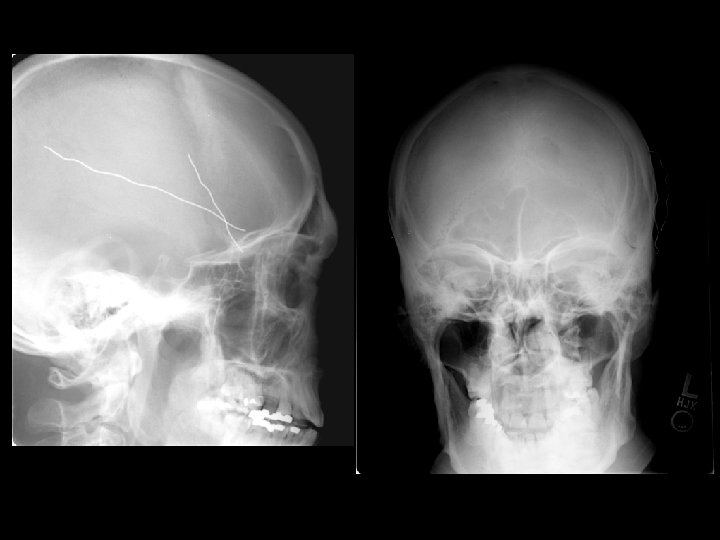

Vỡ xương sọ • Nhiều dạng: – Nứt, lún, rạn nền sọ • Cắt lớp dạng cửa sổ xương • Tổn thương não ở điểm vỡ xương sọ là rất quan trọng • Dường nứt sọ: – Nếu nứt sọ kín, có thể chỉ quan sát theo dõi

Vỡ xương sọ • Vỡ nền sọ: – Thường liên quan đến xương thái dương – Chẩn đoán lâm sàng (CT thường bỏ sót chẩn đoán) • Dấu hiệu đeo kính râm, chảy máu tai, dấu hiệu Battle (tụ máu sau tai), dò nước não tủy qua mũi • Lún sọ: – Phẫu thuật nâng lún: • nếu lớn hơn độ rộng của sọ hoặc • > 5 mm

Chẩn đoán • Chụp sọ: – Phát hiện dị vật – Rẻ tiền và không dùng trong trường hợp nghi có tổn thương não – Dùng cho trẻ nhỏ (<1 tuổi) có vẻ bình thường nhưng có thể có tụ máu dưới da đầu